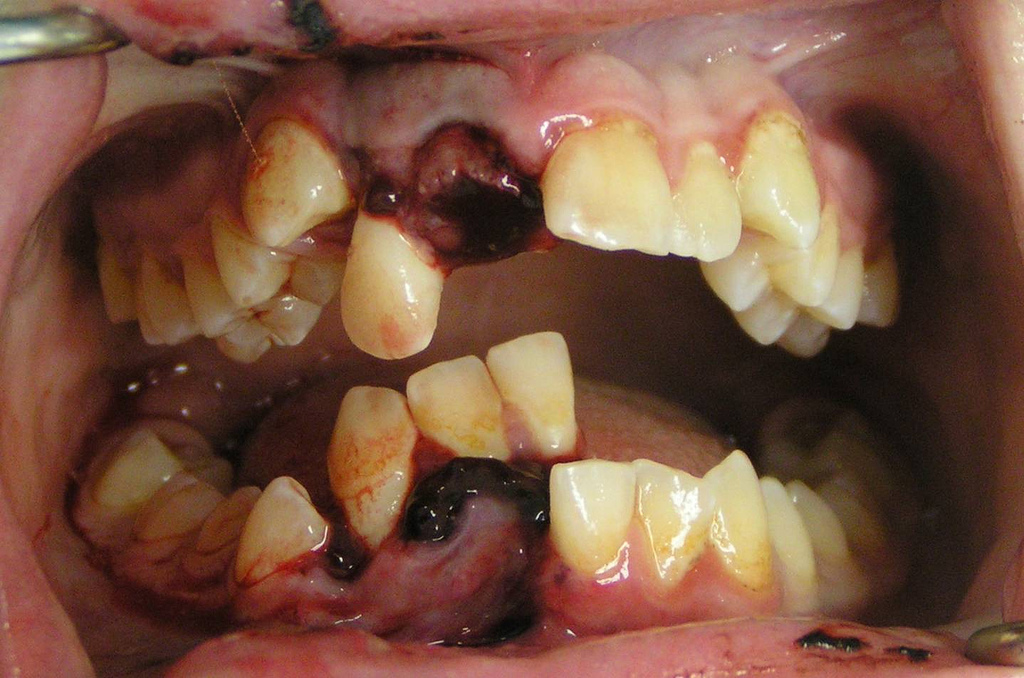

Photo of dental trauma, effecting the right incisors and lower canine, with the avulsion of the upper right central dento-alveolar fracture containing the lower right incisors and canine.